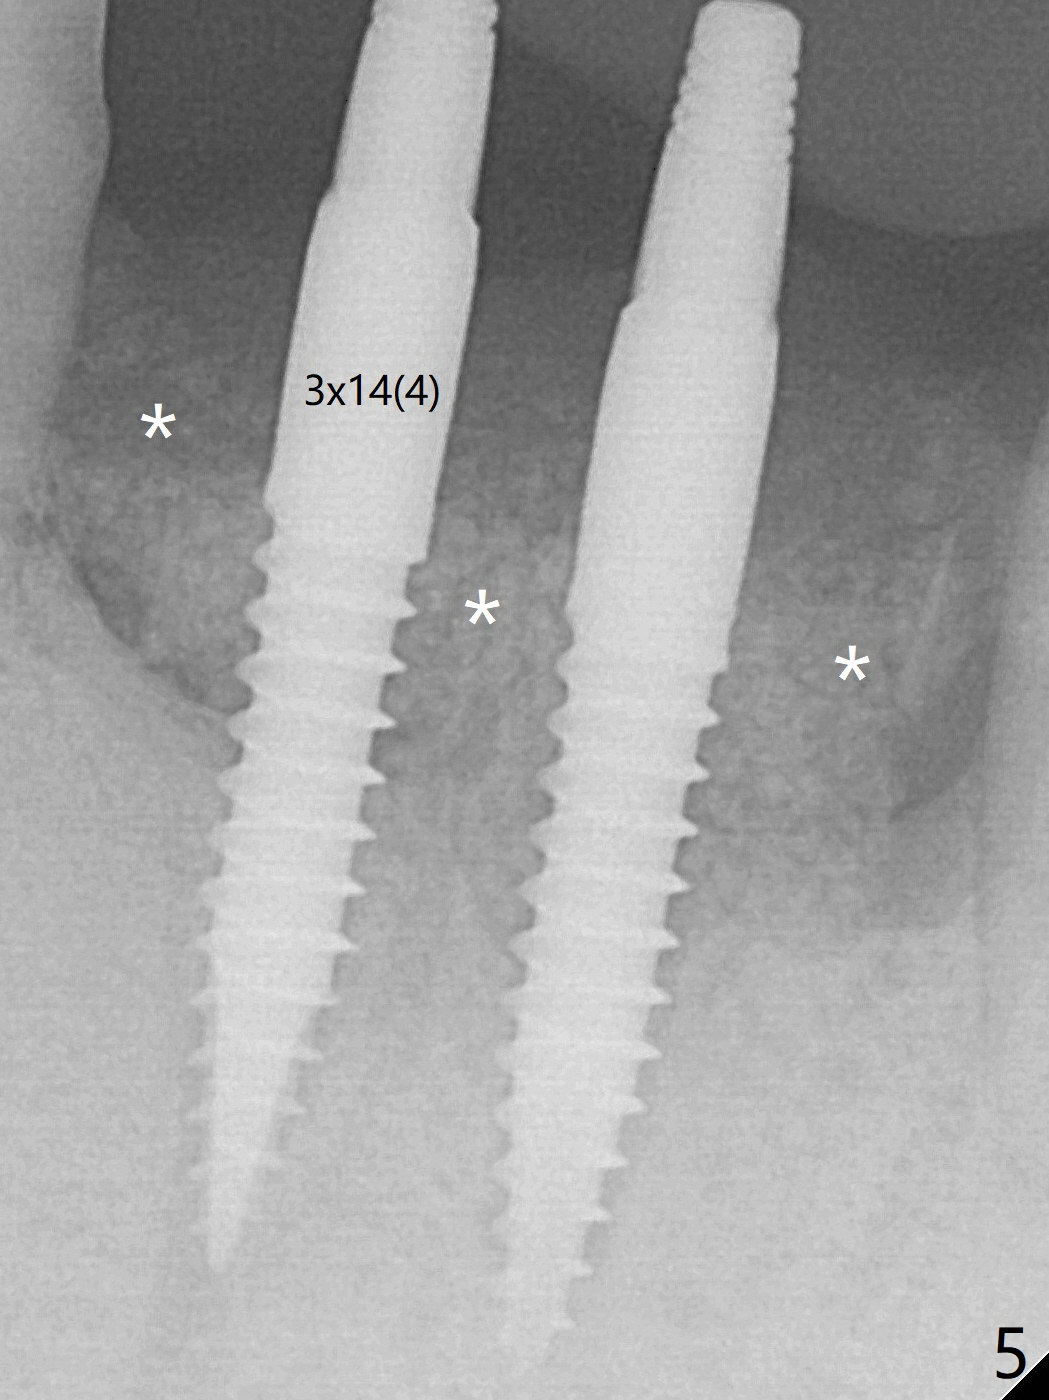

Two of 3x14(4) mm 1-piece implants are placed with ~ 2 mm buccal gap (Fig.3). After Vanilla graft is placed in the bony defects (Fig.5 *) and Osteogen plug, sutures are placed (Fig.4). Most of the grafted bone remains in place 3.5 months postop (Fig.11).